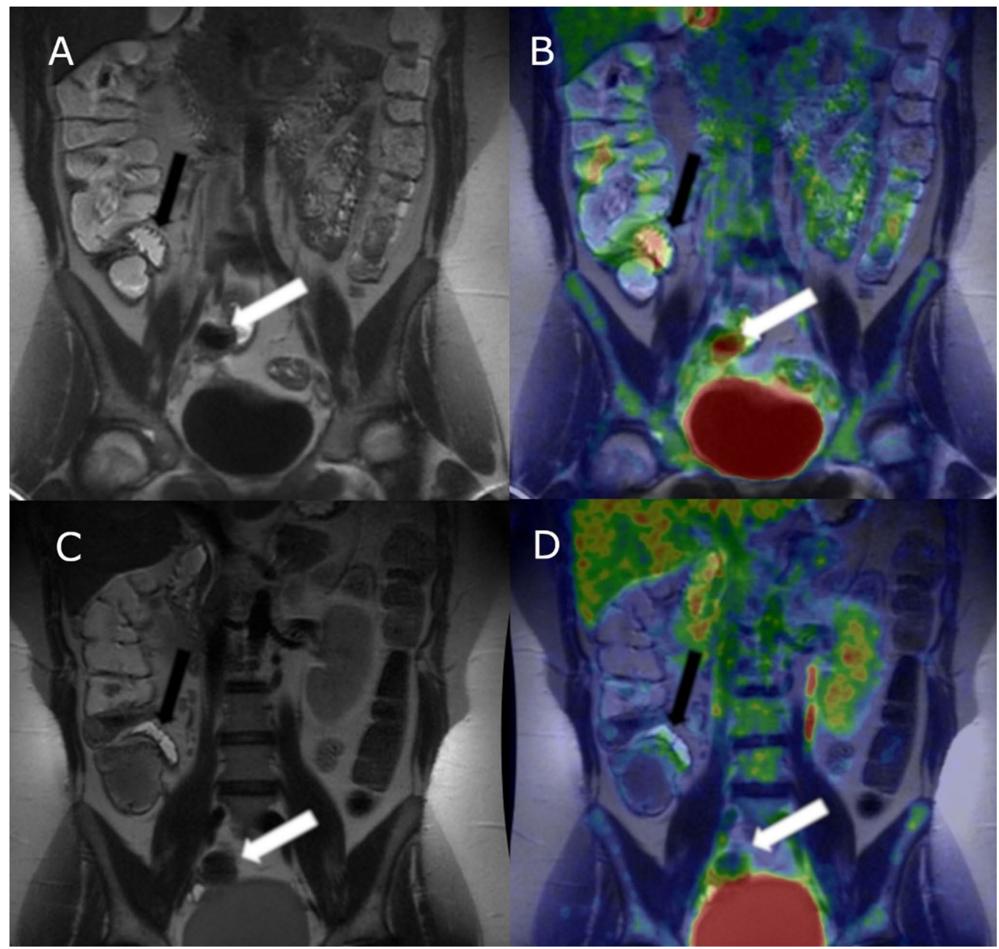

确诊CD患者基线SUVMax显著高于非CD组(3.3 vs 1.9,p=0.0068),证实[18F]-FDG PET-MR对活动性炎症具有鉴别价值。典型病例图像显示,在T2加权MR序列中不明显的炎症灶,通过PET-MR融合成像可清晰辨识。